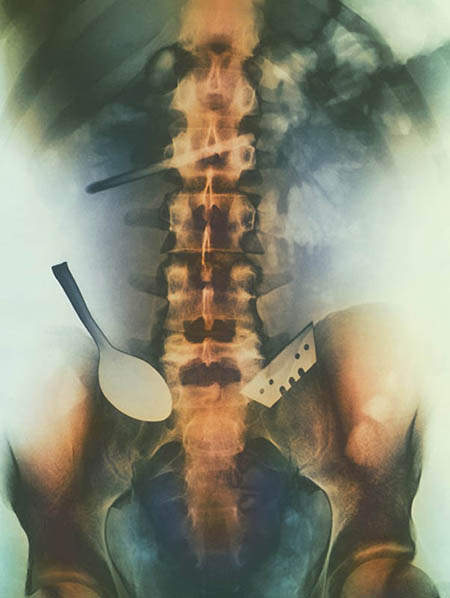

嚥下湯匙和刀的腸